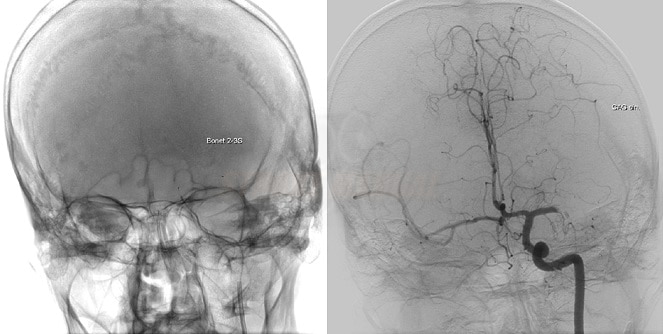

🏥 Suntem bucuroși să vă anunțăm că vom înființa Laboratorul de Angiografie – prima unitate completă dedicată tratamentului patologiei vasculare (neurologică, cardiologică și chirurgicală vasculară) – precum și Compartimentul de Stroke.